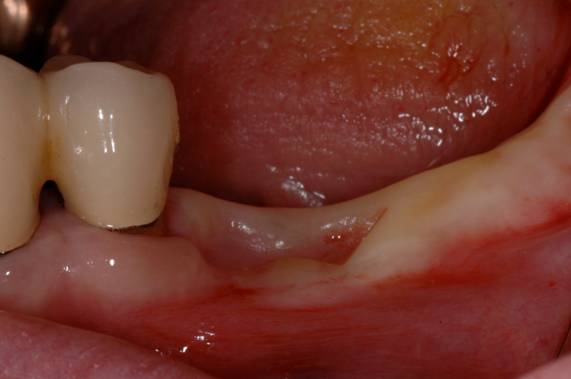

写真は、他院にてインプラント治療を受けた患者さんです。不適切な位置にインプラントが埋められた結果、その上に置く被せ物が不自然に長くなっています。